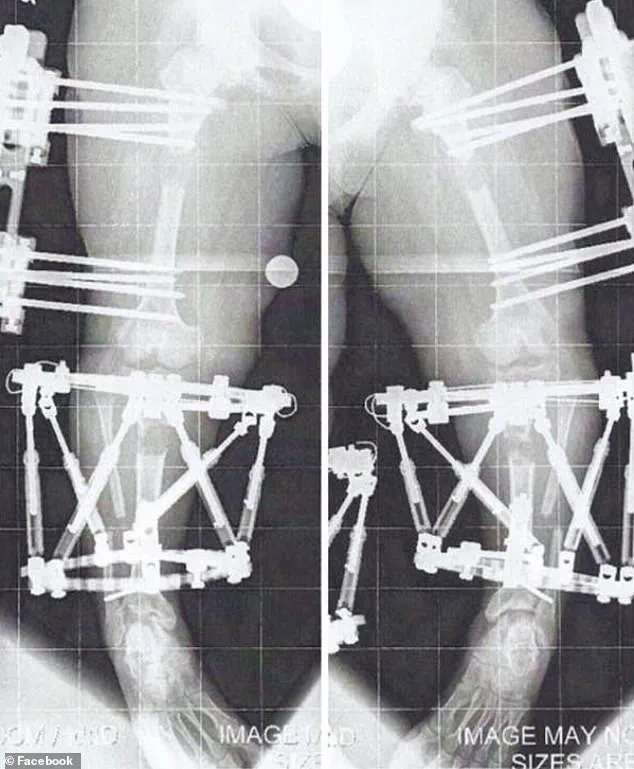

Crews’s first of three limb-lengthening procedures took place in August 2010, when she was 16 years old.

The surgery, which targets the thigh or shin bones, involves implanting either an external fixator or an internal rod to slowly pull the bone segments apart over weeks or months.

The process involves surgically cutting the bone and implanting either an external fixator or an internal rod to gradually lengthen the limb.

For Crews, the initial surgery was accompanied by a grueling recovery, including two to three hours of personal training sessions five days a week and daily exercises and stretches.

By April 2011, her bones had reached the necessary position for the fixators to be removed, marking the end of the active lengthening phase.

This procedure, which involved fixators implanted in her humerus (the upper arm bone) in January 2012, allowed her to remain mobile during the process.